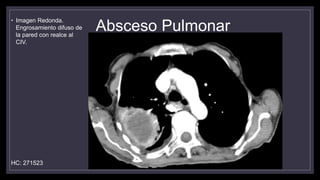

Absceso Pulmonar

• Imagen Redonda.

Engrosamiento difuso de

la pared con realce al

CIV.

HC: 271523